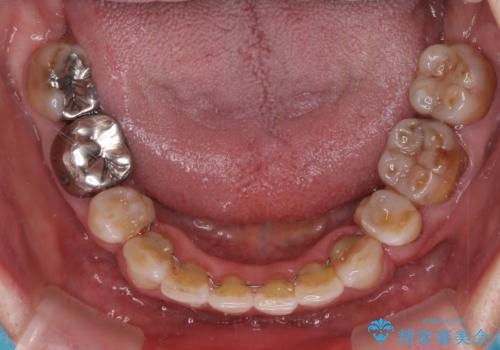

- 突出した口元を引っ込めることを希望して来院された患者様です。

上下左右第一小臼歯4本を抜歯して、口元を改善するワイヤー矯正を行うこととしました。

長年気にされていた口元の突出感が改善されたため、もっと若い時分に矯正をすればよかったと思われていました。